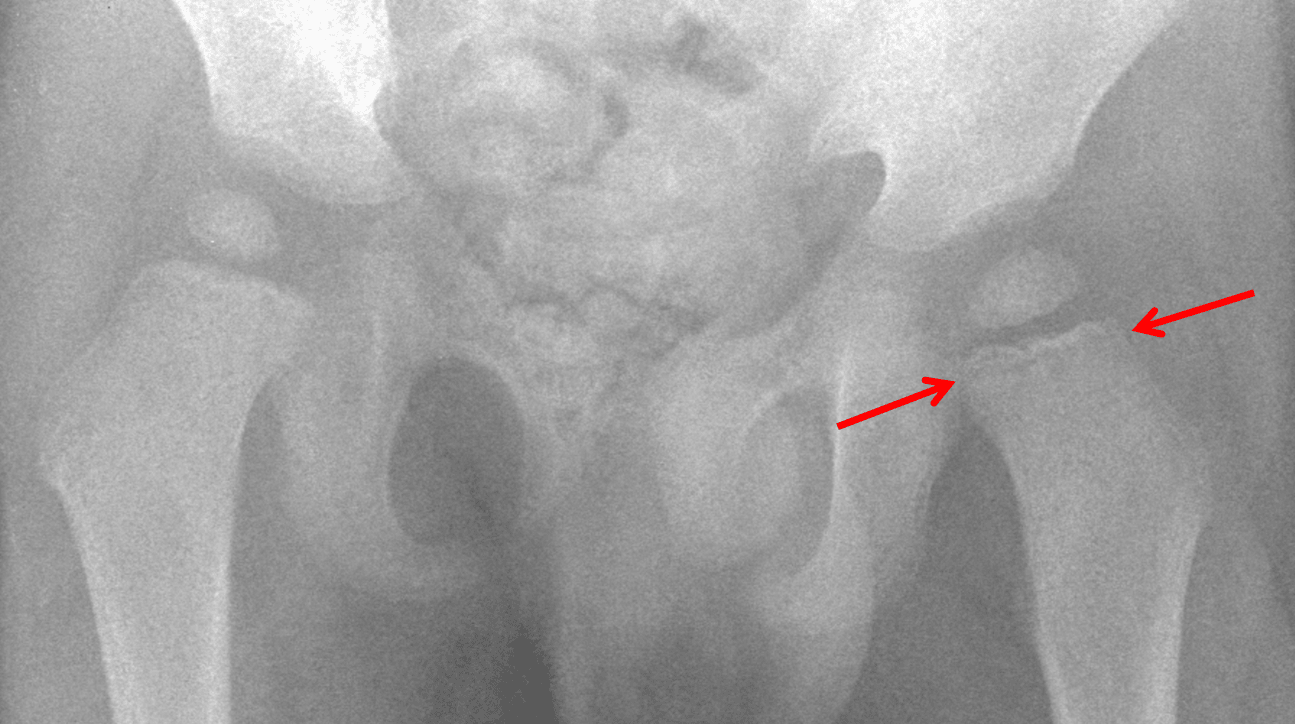

Demographics: 2 years old, Male

Indication: Pain with walking

Leukemic bone involvement

Subtle lucent metaphyseal band in the proximal left femur, which is nonspecific and can be seen in the setting of systemic illness, congenital infections, or malignancy (particularly leukemia and neuroblastoma).

No acute fracture or malalignment.

Red arrows: subtle lucent metaphyseal band.